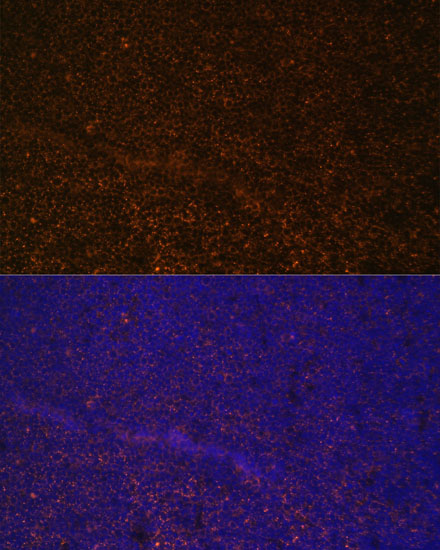

ApplicationWB, IHC, IF; Recommended dilution: WB 1:500 - 1:1000, IHC 1:50 - 1:100, IF 1:50 - 1:100